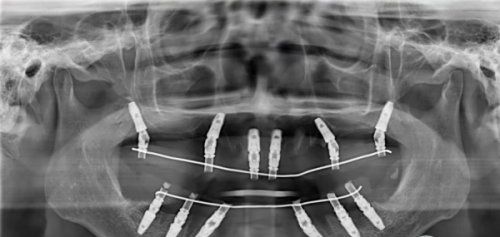

在开始种植牙之旅前,全方面的检查与评估是必不可少的。医生首先会询问患者的病史,了解是否有高血压、糖尿病等全身性疾病,因为这些疾病可能会影响种植牙的成功几率。接着,会进行口腔检查,查看口腔的卫生状况、剩余牙齿的健康情况等。还会借助X光片、CT等影像学检查,严谨了解颌骨的骨量、骨质以及神经血管的位置。只有通过这些详细的检查和评估,医生才能确定患者是否适合种植牙,以及选择合适的种植方案。比如,如果患者骨量不足,可能需要精良行骨增量手术,为后续的种植体植入做好准备。

当各项检查都表明患者适合种植牙后,就进入了关键的植入种植体步骤。在局部麻醉下,医生会在患者的颌骨上切开一个小口,然后使用专精的工具在颌骨上制备一个合适的种植窝,将种植体精细地植入到这个窝内。这个过程就像是为种子找到一个合适的土壤,让它能够在颌骨中“扎根”生长。种植体通常由钛或钛合金制成,具有良好的生物相容性,能够与颌骨紧密结合。植入种植体后,医生会缝合创口,让种植体在颌骨内慢慢愈合。这个愈合过程一般需要三个月左右的时间,期间患者需要遵循医生的嘱咐,注意口腔卫生,避免食用实力强的食物,以确保种植体能够顺利与颌骨融合。